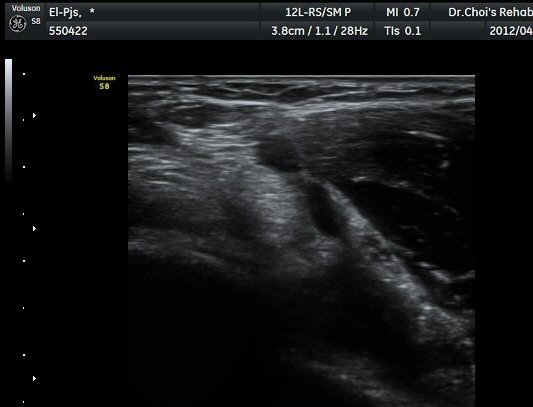

¾Æ·§ÆÈÀ» ¿ÏÀüÈ÷ ȸ³»ÇÑ »óÅ¿¡¼­ ÆÈ²ÞÄ¡°üÀý 1.5cm ¾Æ·¡¿¡ ŽÃËÀÚ¸¦ ȾÀ¸·Î ´ë´Ï ¿ä°ñ°ú

ºñ°ñÀÌ °üÂûµÇ°í ±× »çÀÌ¿¡¼­ À̵ιڱ٠ÈûÁÙ ºÎÂøºÎ°¡ °üÂûµÈ´Ù(±×¸² 7). ŽÂÊÀÚ¸¦ Á¾´Ü¸éÀ¸·Î

À§Ä¡ÇÏ´Ï ¿ä°ñµ¹±â¿¡ ºÎÂøµÈ À̵ιڱ٠ÈûÁÙÀÌ ¶Ñ·ÈÈ÷ °üÂûµÈ´Ù(±×¸² 8).